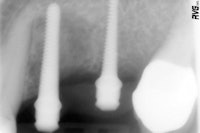

Figure 3 (top): An overview of the system's components, including the manual wrench.Figure 4 (bottom): Radiograph to control the proper position of the Spread-Condense screws.

The Spread-Condense screws can be screwed in with intuition using the hand wrench (figure 3). The laser-etched depth markings are clearly visible during clinical use. Achieved by mechanical clamping, the screw's secure fit allowed for the radiographs to determine the position and the depth without inadvertent aspiration (figure 4).